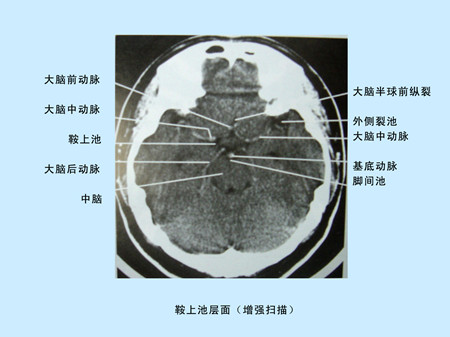

CT(Computed Tomography)是電子計算機X射線斷層掃描技術簡稱。CT的工作程序是這樣的:它根據(jù)人體不同組織對X線的吸收與透過率的不同,將測量所獲取的數(shù)據(jù)輸入電子計算機,電子計算機對數(shù)據(jù)進行處理后,攝下人體被檢查部位的斷面或立體的圖像,可發(fā)現(xiàn)體內(nèi)任何部位的細小病變。CT圖像是重建圖像。

CT由于它的特殊價值,已廣泛應用于臨床。但CT設備比較昂貴,檢查費用偏高,某些部位的檢查,價值,尤其是定性,還有一定限度,所以不宜將CT檢查視為常規(guī)手段,應在了解其優(yōu)勢的基礎上,合理的。在頭部檢查中,CT可用于腦出血,腦梗塞,動脈瘤,血管畸形,各種腫瘤,外傷,骨折,先天畸形等方面的。

CT平掃及增強掃描腦組織圖像顯示                                                       超聲經(jīng)顱多普勒檢測時顯示圖像